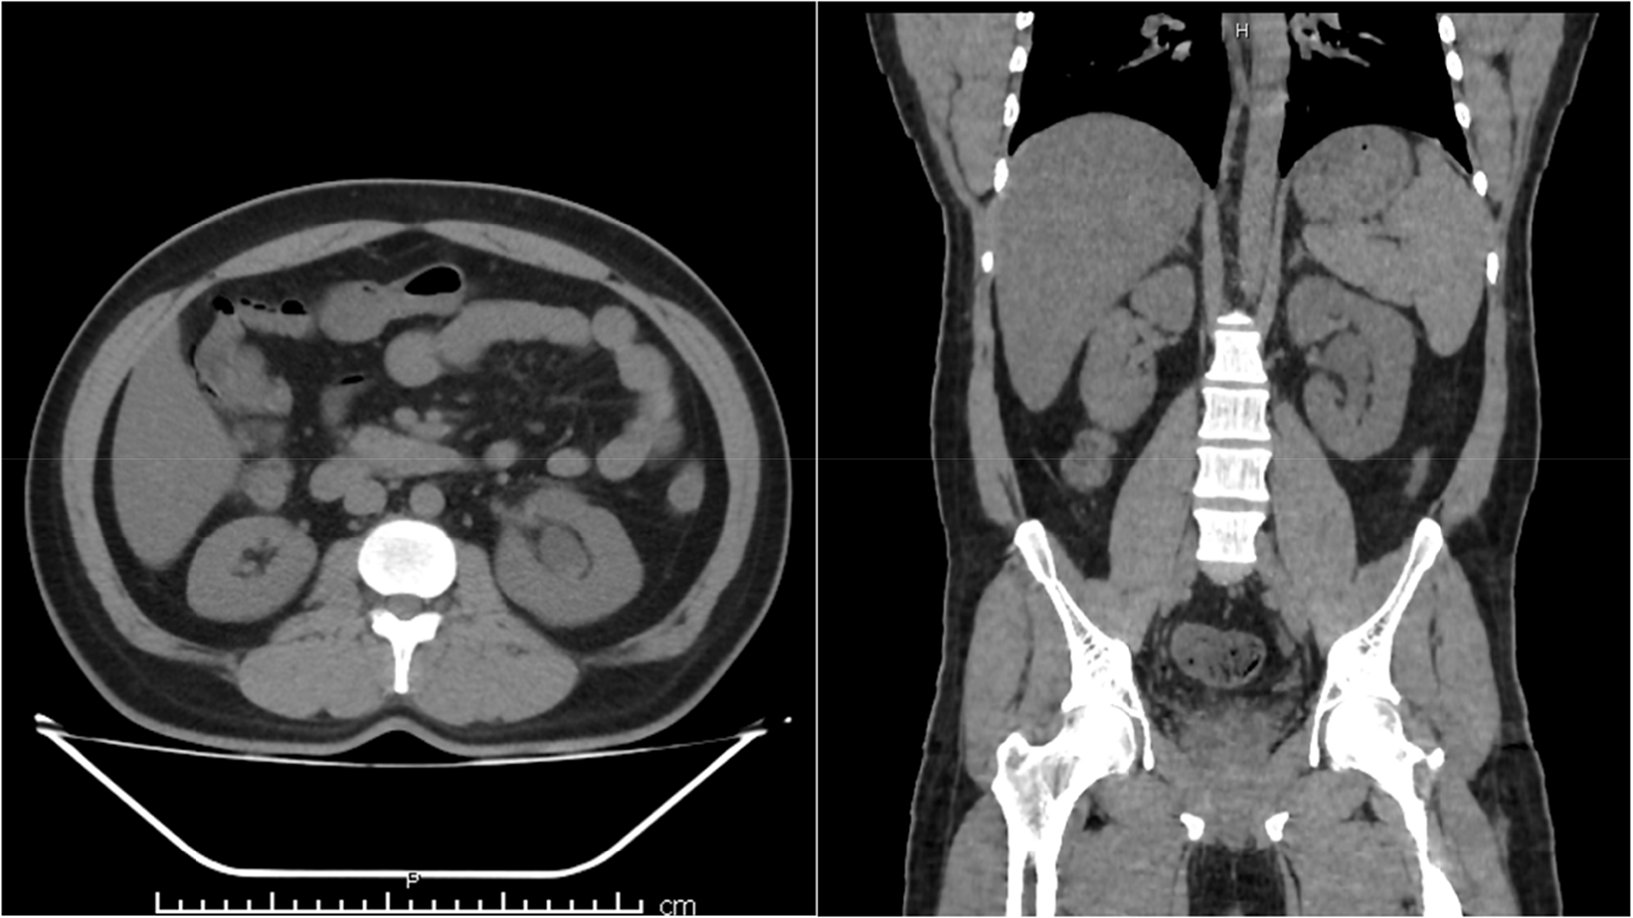

On investigations, the renal function was mildly deranged with creatinine of 2.4 mg/dl, enlarged left kidney with minimal hyperechoic content mild hydronephrosis on ultrasound examination. Further imaging with a non-contrast computed tomography scan showed a moderately hydronephrotic left kidney (Figure 2). Given persistent raised creatinine and features of obstructive uropathy intervention with a flexible ureteroscope was done, which showed thick cheesy material with mucous strands within the pelvi-calyceal system (Figure 3). A double J (DJ) stent was placed after clearing most fungal balls piecemeal. Oral Voriconazole 200 mg twice daily was started and continued for 6 weeks. The recovery was uneventful with creatinine returning to normal levels. The retrieved material, on microscopy, showed large colonies of septate hyphal forms with parallel walls and slender acute-angled branching, consistent with Aspergillus species (Figure 3).

FIGURE 2. Axial and coronal cut section showing left hydronephrotic kidney